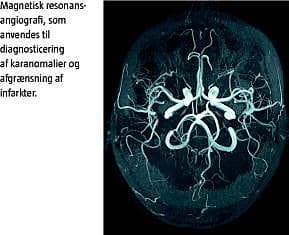

Som led i udredningen af patienter, hos hvem man har mistanke om cerebralt insult, vil der tidligt i sygdomsforløbet blive gennemført billeddannelse med computertomografi (CT) eller magnetisk resonans (MR)-skannin g. Oftest bruges CT til den akutte diagnostik. CT er velegnet til detektering af blødninger. CT-angiografi kan anvendes til diagnostik af karpatologi. MR-skanning, specielt med kontrast, er bedre, når diagnosen AIS skal stilles, og MR-venografi er bedst, når man skal detektere CSVT. Cerebral angiografi anvendes specielt, når man skal finde karanomalien ved ICH, hvor denne undersøgelsesmetode kan give mere diagnostisk information end MR-angiografi [7, 8, 13]. Den videre udredning indbefatter blodprøver i form af rødt og hvidt blodbillede, infektionsprøver, blodsukker, lipider, trombofiliudredning, immunologisk udredning og metaboliske undersøgelser samt evt. hæmoglobinelektroforese (til undersøgelse for SCD), afhængigt af hvilken ætiologi der er mistanke om (Tabel 2 ). Lumbalpunktur (inkl. virusundersøgelse), ekkokardiografi for at diagnosticere kardiel patologi samt eventuelt Doppler-ultralyd af halskarrene for at diagnosticere dissekerende aneurismer skal også overvejes [13].